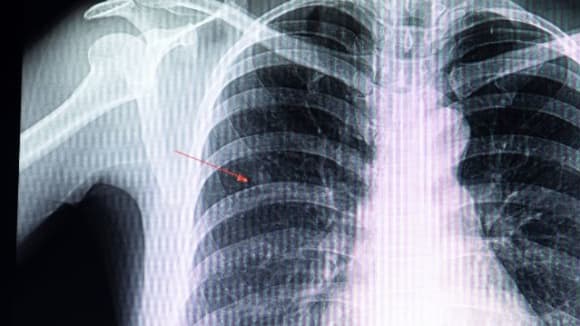

Certains nodules correspondent à des tumeurs non agressives et sans danger. Toutefois, la présence de nodules peut également révéler un cancer du poumon. Parfois, ils témoignent de la propagation d’un cancer provenant d’un autre organe, comme le sein ou le côlon, sous forme de métastases. C’est pourquoi les médecins s’attachent à identifier précisément la nature du nodule détecté, notamment à l’aide d’une radiographie ou, de manière plus fiable, grâce à un scanner.

Un nodule est une masse souvent solide de forme arrondie, constituée de cellules et/ou de tissus. Lorsqu’il se situe sous la peau, il peut parfois être perçu au toucher. Cependant, s’il est localisé plus en profondeur, comme dans les poumons, il reste indétectable par palpation. Selon sa taille, il peut être mis en évidence lors d’un examen d’imagerie médicale, tel qu’une radiographie ou un scanner, et souvent découvert de manière fortuite. Bien que la majorité des nodules soient bénins et constituent une anomalie fréquente chez l’être humain, certains peuvent révéler la présence d’une tumeur maligne.